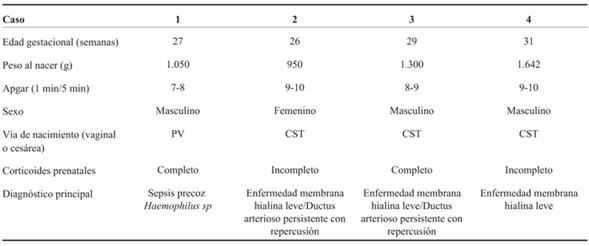

A continuación se detalla la experiencia de los primeros cuatro casos realizados (el primer caso fue el 29 de setiembre de 2017). Contamos con la aprobación del protocolo del Comité de Ética del hospital y con el consentimiento informado y firmado de los padres.

Caso 1

RN, sexo masculino, 1.050 g, nacido a las 27 semanas de edad gestacional (EG) por vía vaginal. El nacimiento vaginal espontáneo ocurrió 60 horas después de la rotura prematura y prolongada de las membranas ovulares, habiendo completado previamente el curso completo de corticoides para la maduración pulmonar fetal. Inmediatamente después del nacimiento, el RN fue colocado en la pared abdominal materna en una bolsa plástica, manteniendo la circulación fetoplacentaria. Simultáneamente, un operador, en este caso residente de Neonatología, administró un bolo de 5 ml de Survanta® (previamente cargado en la jeringa y llevado a temperatura ambiente) con una sonda de alimentación orofaríngea colocada en la hipofaringe antes del inicio de la respiración del RN. Al mismo tiempo, se colocó la pieza nasal para administrar presión positiva continua en la vía aérea. Este procedimiento tomó los primeros 5 segundos de vida, lo cual fue calculado según análisis de video realizado posterior al nacimiento. Una vez que las piezas nasales estuvieron en posición, una insuflación mantenida de 5 segundos fue aplicada con presión inspiratoria positiva (PIP) de 20 cm H2O y presión positiva del final de la espiración (PEEP) de 5 cm H2O durante 5 segundos, con oxígeno al 100%, único disponible en el lugar de recepción. El RN inició respiraciones espontáneas en los primeros 30 segundos posnacimiento. El cordón fue pinzado a los 2 minutos después de nacer. El RN fue tratado con presión positiva continua de la vía aérea (CPAP) aplicada mediante pieza nasal. De inmediato se redujo la FIO2, siendo a la hora de vida de 23% y en la segunda hora de 21%. Se inició nutrición enteral con leche materna fresca en las primeras horas de vida. El RN no recibió inotrópicos. Presentó SDR leve, coincidiendo con suficiente aireación pulmonar en la radiografía de tórax, por lo que no requirió una segunda administración de surfactante. Los resultados iniciales de laboratorio mostraron desarrollo de Haemophylus influenza en sangre, con lo que se realizó diagnóstico de sepsis precoz que fue tratada hasta los 21 días con cefalosporina de tercera generación. El estudio de la placenta reveló la confirmación del germen Haemophylus influenza, coincidiendo con los hallazgos iniciales. La ecografía transfontanelar realizada al tercer día de vida mostró hemorragia intraventricular (HIV) grado III a derecha y grado II a izquierda, estando al mes de vida incambiada respecto a los hallazgos iniciales, con signos de hemorragia evolucionada (reabsorción y reorganización del sangrado), sin desarrollo de hidrocefalia. En la evolución, el paciente presentó buen crecimiento en percentil 10, según curvas de la Organización Mundial de la Salud (OMS) para su edad gestacional. Actualmente el paciente se encuentra en seguimiento de su desarrollo en la policlínica de RN de alto riesgo del Hospital Universitario, y muestra una adquisición de conductas con leve atraso para la edad gestacional corregida, según la pancarta de desarrollo de CLAP-OPS utilizada por el Ministerio de Salud, validada como instrumento para la pesquisa de problemas de desarrollo en menores de 5 años en Uruguay11. La última ecografía encefálica a los 3 meses y 20 días de edad gestacional corregida, informa ventrículos de dimensiones normales, a nivel de zona de sangrado reorganización del coágulo sin otros elementos que afecten la sustancia blanca.

Caso 2

RN, sexo femenino, 915 g, 26 semanas de EG. Segunda gestación, embarazo bien controlado que se interrumpió por síndrome de HELLP (según su sigla en inglés, significa hemólisis, aumento de enzimas hepáticas y trombocitopenia). Maduración pulmonar fetal incompleta. Cesárea de urgencia, nacimiento del RN en capullo, se colocó en bolsa plástica estéril para evitar pérdidas de calor. Siguiendo el protocolo descrito en el caso 1 se realizó la recepción. Brevemente: previo al pinzamiento de cordón umbilical y a la primera inspiración se instiló bolo de 4 ml de Survanta® en orofaringe a través de sonda de alimentación. Simultáneamente se colocó pieza de CPAP nasal y se aplicó una insuflación mantenida de 20 cm de H2O durante 5 segundos, manteniendo una PEEP de 5 cm de H2O durante todo el procedimiento con FiO2 de 1. Se pinzó el cordón al cesar el flujo placentario y se trasladó a una termocuna manteniendo respiraciones espontáneas, por lo que continuó en CPAP y se trasladó a UCIN de la misma institución. A la hora de vida se obtuvo radiografía toracoabdominal (Figura 1), sin elementos de enfermedad de membrana hialina. A las 2 horas de vida se logró FiO2 de 0,21. Recibió dos dosis adicionales de surfactante por técnica mínimamente invasiva, dado el aumento de requerimientos de oxígeno en la evolución. A las 48 horas de vida, diagnóstico de ductus arterioso permeable con repercusión hemodinámica, que se trató con paracetamol intravenoso durante tres días, con evolución favorable, confirmándose cierre ecográfico al cuarto día de vida. Ecografías encefálicas normales a las 24 horas de vida, al mes de vida y a las 36 semanas de EGC. No contamos con el seguimiento al alta de esta paciente.

Caso 3

RN, sexo masculino, 1.300 gramos, 29 semanas de EG. Madre hipertensa crónica. Embarazo bien controlado, complicado con diabetes gestacional. Recibió inducción de la maduración pulmonar fetal completa a las 29 semanas. Cesárea de urgencia por preeclampsia severa, extracción podálica, se colocó en bolsa de polietileno. Tal como en los casos 1 y 2, se administró surfactante orofaríngeo 5 ml Survanta® a través de sonda de alimentación en la orofaringe, concomitante administración de presión positiva continua en la vía aérea, con insuflación sostenida de 5 segundos, PIM 20 cm H2O, PEEP 6 cm H2O, flujo 8 L/min, FiO2 1. Dichos procedimientos se realizaron con circulación fetoplacentaria intacta. Se mantuvo en CPAP desde el ingreso a la unidad hasta los ocho días de vida. Dada la persistencia del trabajo respiratorio se administraron dos dosis de surfactante por traqueoclisis. A las 27 horas de vida se diagnosticó un DAP, logrando cierre farmacológico a las 72 horas. Ecografía encefálica normal a las 24 horas de vida y en su evolución hasta el alta de UCIN. Crecimiento en percentil 50-75 según curvas de la OMS para su EG, desarrollo con adquisición de conductas normales para EG. Seguimiento por pediatra en su ciudad de origen y en policlínica de seguimiento de recién nacidos de alto riesgo en Hospital Universitario, mediante el mencionado instrumento para la pesquisa de problemas del desarrollo11).

Caso 4

RN, sexo masculino, 1.642 g, 31 semanas de EG. Embarazo insuficientemente controlado. Recibió inducción de la maduración pulmonar fetal incompleta una hora antes del nacimiento. Cesárea de urgencia por preeclampsia de difícil control. Extracción cefálica, se colocó en bolsa de polietileno, y siguiendo el protocolo de los casos previos se instilaron 6 ml de surfactante orofaríngeo Survanta® a través de sonda de alimentación orofaríngea. De manera concomitante se aplicó una insuflación sostenida previo a la primera respiración espontánea, con una PIM de 20 cm H20, PEEP 6 cm H20, flujo de 8 L/min, FiO2 1, por 20 segundos, manteniendo la circulación fetoplacentaria. En la evolución se disminuyeron los requerimientos de oxígeno, quedando en CPAP. No requirió dosis posteriores de surfactante. Ecografía encefálica normal a las 24 horas de vida y en la evolución posterior hasta el alta de UCIN. El crecimiento fue en percentil 50-75 según curvas de la OMS; en el desarrollo, la adquisición de conductas fueron normales para la edad gestacional y el seguimiento se realizó en policlínica con pediatra de referencia y policlínica de seguimiento de recién nacidos de alto riesgo del Hospital Universitario mediante el mencionado instrumento para la pesquisa de problemas del desarrollo11).

Como se muestra en la (Tabla 1) y (Tabla 2), que resumen nuestra serie de casos, esta técnica no ha determinado complicaciones y ha logrado mejorar la estabilización respiratoria en la transición a la vida extrauterina. Por lo tanto, al igual que en publicaciones previas, la técnica es segura, pues no se encontraron efectos adversos durante ni posteriormente a su administración.